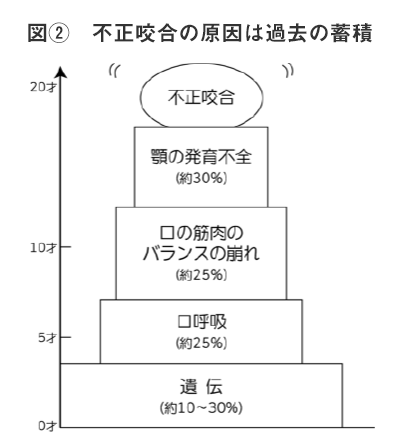

西村歯科医院では、不正咬合の原因は、図②に指すように乳幼児からの生活習慣の業績と考えています。

つまり、12才以降の不正咬合の矯正(顎の発育不全)の治療は、原因の30%しか改善されていないと考えています。

他の遺伝因子10~30%を除く40%の原因は、そのまま放置され、抜歯をして、歯並びを整える矯正をしている場合が多いのではないでしょうか?